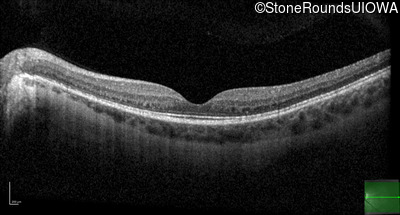

Optical Coherence Tomography - Right - 20/40 +1

Exemplar / OCT Stack